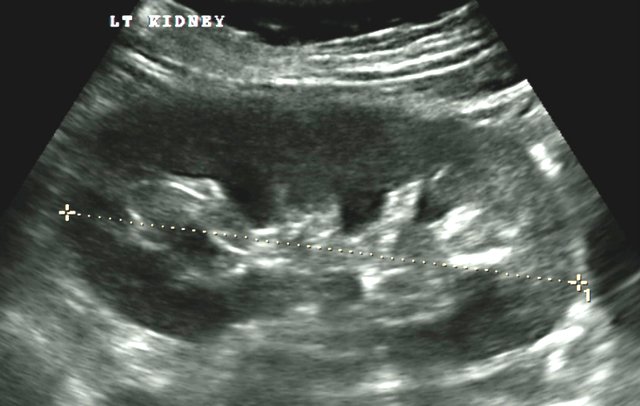

The scan is performed to exam the kidneys and bladder and (for men includes prostate), we will look at the size, shape and the appearance of the kidneys, bladder.

The procedure may detect kidney stones, cysts and tumours alongside other pathologies. It will also enable to look for any caused of urine infections.